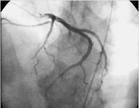

冠脈造影冠狀動脈瘺是否引起臨床症狀,與瘺發生的部位以及瘺的大小相關,小動脈瘺一般不引起臨床症狀,不需要手術治療。多發和大冠狀動脈瘺可導致心肌缺血和心肌梗死,少數患者還可以發生充血性心力衰竭。部分冠脈畸形不會導致心肌灌注的明顯異常,稱之為“良性”冠脈畸形;而部分冠脈畸形因走行於主肺動脈間或開口處的狹窄而致心肌缺血甚至猝死,稱之為“惡性”冠脈畸形。冠脈畸形的早期及正確診斷甚為重要。冠狀動脈畸形是一種少見的先天性心血管畸形,冠狀動脈造影是診斷冠狀動脈畸形的金標準。